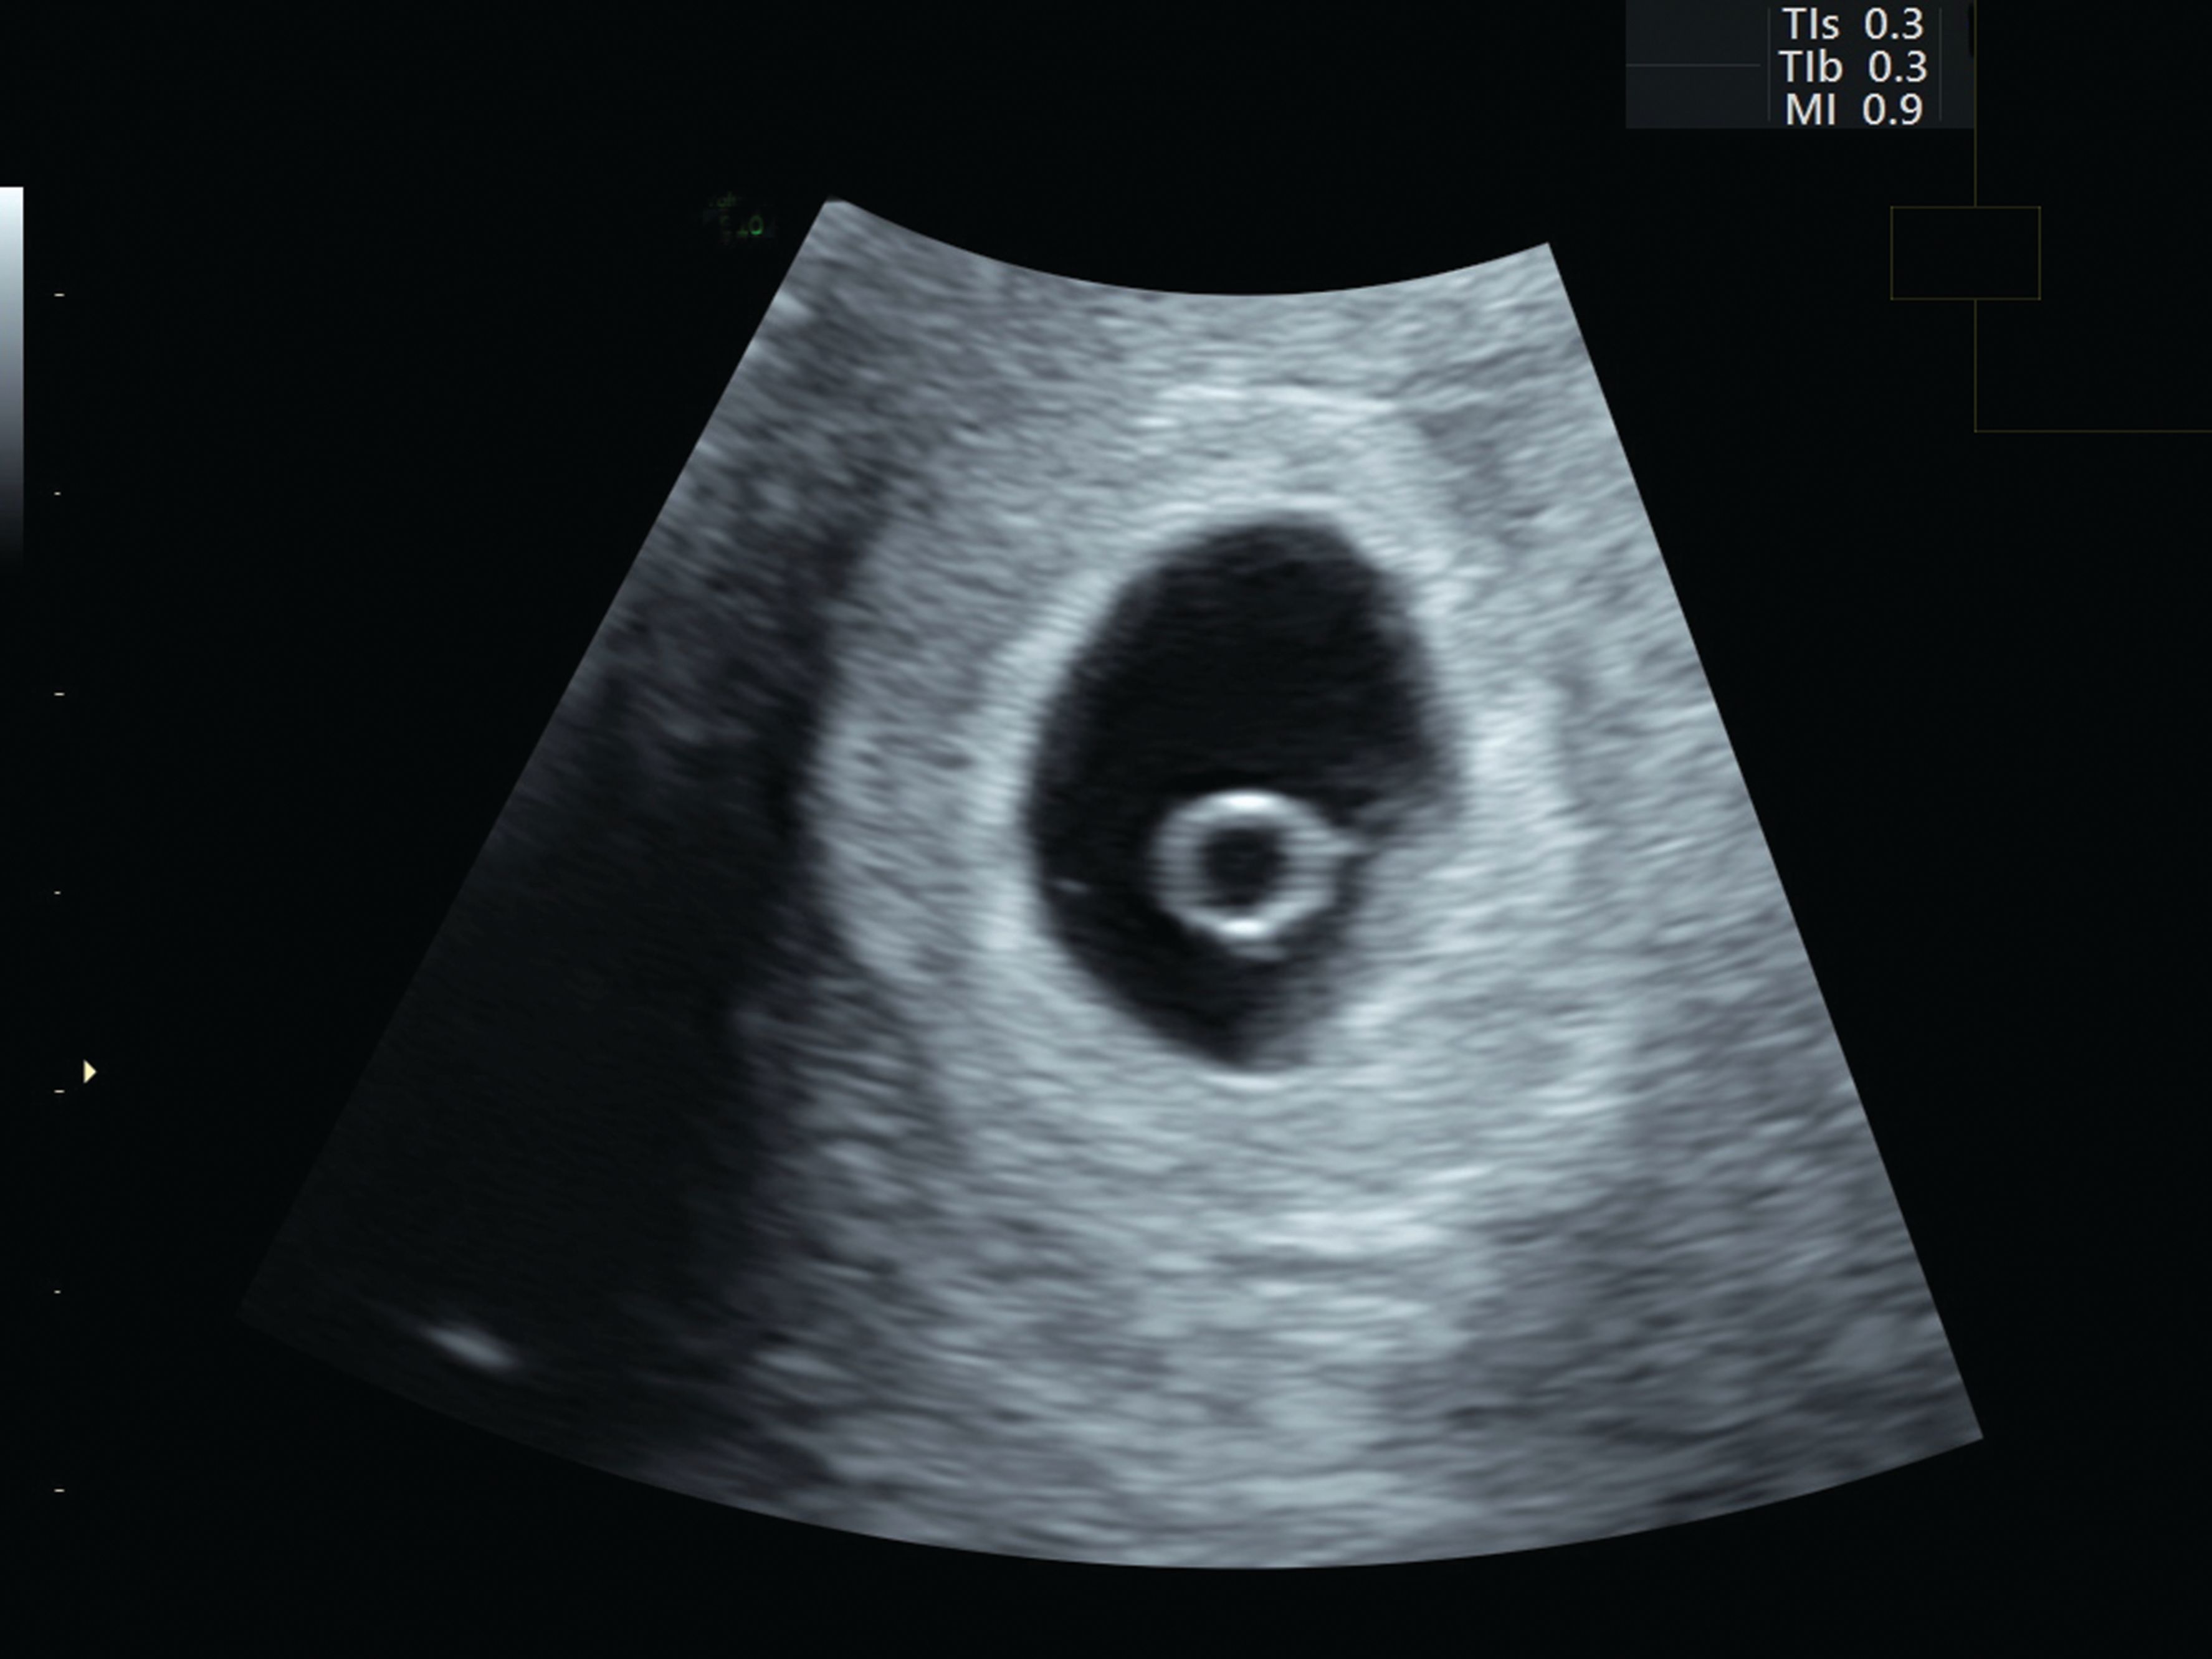

The yolk sac is first visible at 5 weeks and it is always present by 5 weeks and 4 days There are lacunary structures cavities or spaces at the site of implantation The embryonic pole appears adjacent to the yolk sac, soon showing cardiac activity Since the connecting stalk is short, the embryonic pole is found near the wall Re Anyone have an ultrasound at 5 weeks 3 days or 4? I had my first ultrasound today and the baby is measuring earlier than we thought I assumed I was 8 weeks 5 days today but the baby measured at 8 weeks 0 days The doctor said everything looks great and she expects a healthy pregnancy She

This a fantastic video showing the stages of baby growth from 5 to 9 weeks and also in 3d It is annotated so can be used for learning by medical profession#11 bestmum, RNmommy Mom of 2 and Pregnant!Gestational Age Week 5 (Fetal Age Week 3) Around 5 weeks, the gestational sac is often the first thing that most transvaginal ultrasounds can detect This is seen before a recognizable embryo can be seen Within this time period, a yolk sac can be seen inside the gestational sac

Baby 5 weeks 3 days ultrasound- 5 week 3 days Ultrasound Discussion in 'Pregnancy First Trimester' started by januarymom12, I had a scan at 5 weeks 3 days and we saw only a gestational sac No yolk , just an empty sac , 2 weeks later saw baby heart beat I'm 13 weeks today ! (In the United States, the chance of having twins is about 3 percent) Be aware, though, that sometimes 6 weeks is too early to tell Location The ultrasound can locate where the embryo is implanted